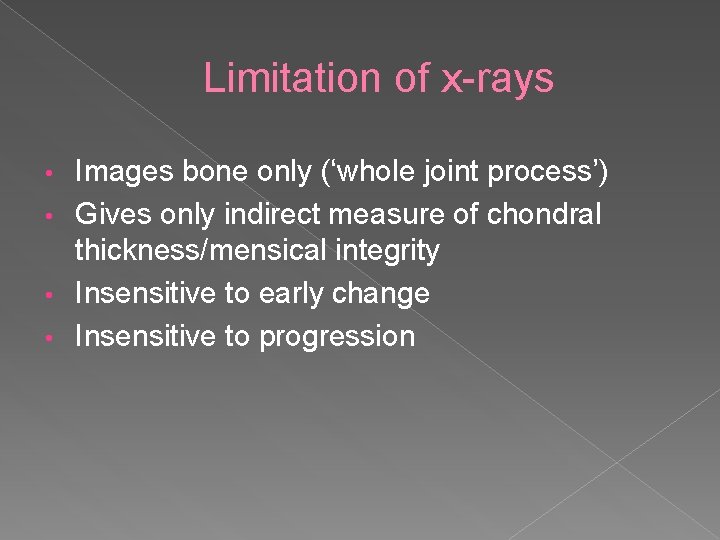

Limitation of x-rays Images bone only (‘whole joint process’) • Gives only indirect measure of chondral thickness/mensical integrity • Insensitive to early change • Insensitive to progression •